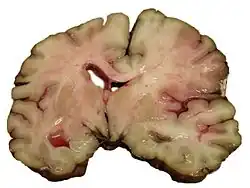

A slice of brain from the autopsy of a person who had an acute middle cerebral artery (MCA) stroke

Stroke can be classified into two major categories: ischemic and hemorrhagic.[20] Ischemic stroke is caused by interruption of the blood supply to the brain, while hemorrhagic stroke results from the rupture of a blood vessel or an abnormal vascular structure.